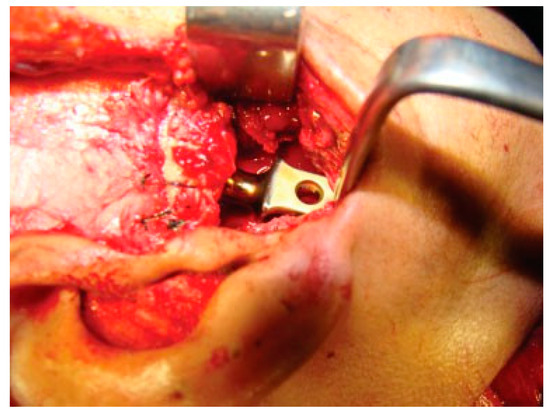

Figure 10. Condylar head titanium reconstruction plate with temporalis muscle interpositioning.

The unique ability of the CCG to remodel into neocondyle could be well appreciated on the digital OPG and CT scan of the patient. The length and width of the neocondyle was very much comparable to the length of the condyle on the unaffected side at 6 years follow-up. Thus, the neocondyle formed using the costochondral cartilage was identical to the unaffected mandibular condyle both structurally and functionally. Poor socioeconomic conditions and lack of awareness coupled with poor primary health care facilities lead many of these unfortunate patients to live with this debilitating condition well into adulthood. Five such adult patients with age ranging from 17 to 36 years reported to us for treatment of TMJ ankylosis. In all these patients, ankylotic bony mass extends beyond the boundaries of the joint capsule. Alloplastic reconstruction after the release of ankylosis was our method of treatment, although high cost of condylar prosthesis led us to use 2.4 mm condylar head reconstruction plate along with temporalis muscle interpositioning in these patients. Interpositional grafts may fail to restore the ramal height in bilaterally ankylosed adult patients, so alloplastic condylar reconstruction may become the preferred choice. Advantages of alloplastic TMJ reconstruction are that the physical therapy can begin immediately, there is no need for a secondary donor site, surgery time is decreased, and alloplasts can be constructed in such a way as to mimic the normal anatomic contours of the structures they are to replace [17,18]. Wolford and Karras have suggested autologous fat transplantation as a useful adjunct to prosthetic TMJ reconstruction, as it minimizes the occurrence of excessive joint fibrosis, heterotopic calcification, and improves the range of motion [19]. However, they have categorically stated in their discussion that heterotopic bone formation is seen in multiple operated joints and joints with previously failed alloplastic implants. Another method to combat heterotopic bone formation is the use of 10 Gy of irradiation in five fractionated daily doses in the immediate postoperative period [20]. In our series, none of the patients reported with heterotopic bone formation possibly because they had undergone a single surgical procedure for managing TMJ ankylosis. The risk of fossa perforation could have been taken care by interpositioning of temporalis muscle in all these patients.

The vertical ramal height was restored at least on one side using metallic condylar head in cases of bilateral TMJ ankylosis (Figure 10). Postsurgery, the patients with alloplastic condylar head were more compliant to physiotherapy during the immediate postoperative period possibly due to restoration of anatomy. The range of mandibular movements was recovered earliest and best in cases where alloplastic condylar head was implanted. The postoperative mouth opening was 45.6 mmwhich is maximum in our entire series of 22 patients where increased mouth opening (p < 0.001; Table 2 and Table 3) could be attributed to patients being adult with full development of stomatognathic apparatus as compared with younger patients. Long-term follow-up showed better adaptation because of its ability to conform to the associated bony contours as compared with any other autogenous material used in our series.